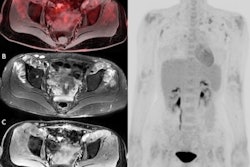

A 68-year-old woman who met the FUO criteria. F-18 FDG-PET/CT torso imaging shows longitudinal uptake along the aorta and the large vessels, pathognomonic for giant cell arteritis (arrows). The patient showed only minimal clinical symptoms for vasculitis. Causal anti-inflammatory therapy with oral cortisone was started, to which patient responded well. Image courtesy of Scientific Reports.The largest part of final diagnoses was assorted to infectious diseases (109/300 patients, 36.3%) followed by autoimmune/rheumatic diseases (51/300 patients, 17%) and malignancy (33/300 patients, 11%), according to the findings.